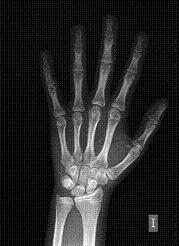

Dependiendo de cada paciente el diagnóstico necesitará una serie de pruebas y estudios complementarios, como pueden ser radiografías, fotos, o modelos de estudio montados en articulador ( este es un dispositivo que simula los movimientos mandibulares).

En algunos pacientes pueden ser necesarias valoraciones concretas dirigidas a diagnosticar alguna patología específica.